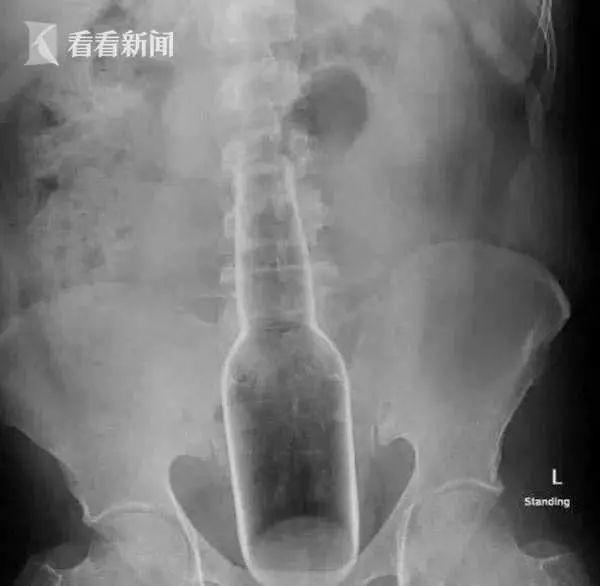

近日一张玻璃瓶从肛门塞进直肠,顶在腹部的X光片,让花姐感到颇感震惊,十分好奇这是什么操作?

原来一名男子在东莞市中西医结合医院的肛肠科求诊,医生竟从一名男子的直肠内取出了一个18厘米长的花露水瓶。

一个这么大的瓶子怎么会塞入体内呢?在医生追问下,患者才透露出了实情。说自己肛门瘙痒难耐,于是就用花露水瓶去抠,结果一不小心就进肛门里了。